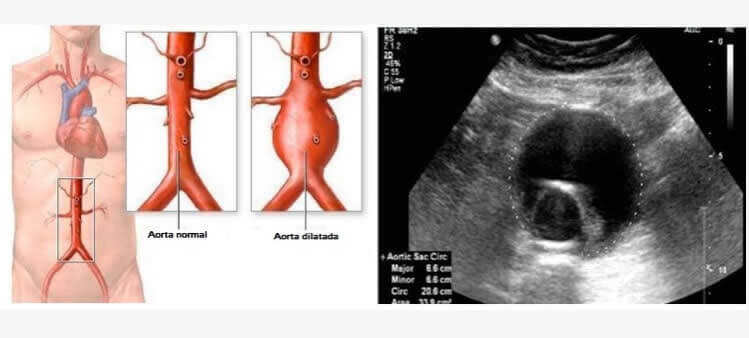

Aneurisma da Aorta Abdominal

Um aneurisma consiste na dilatação de um segmento da artéria. A dilatação se deve à fraqueza desenvolvida numa porção da parede arterial. Assim como um balão, o alargamento do aneurisma estende-se pelas camadas da parede arterial, que cada vez mais fina, compromete a capacidade elástica deste trajeto correndo o risco de romper-se. O local mais comum para um aneurisma da aorta é o abdômen, abaixo do nível das artérias renais. Um aneurisma da aorta abdominal (AAA) pode não ser detectado em exames de rotina, mas a ultrassonografia fornece uma avaliação não invasiva precisa e segura para medir o tamanho da aorta.